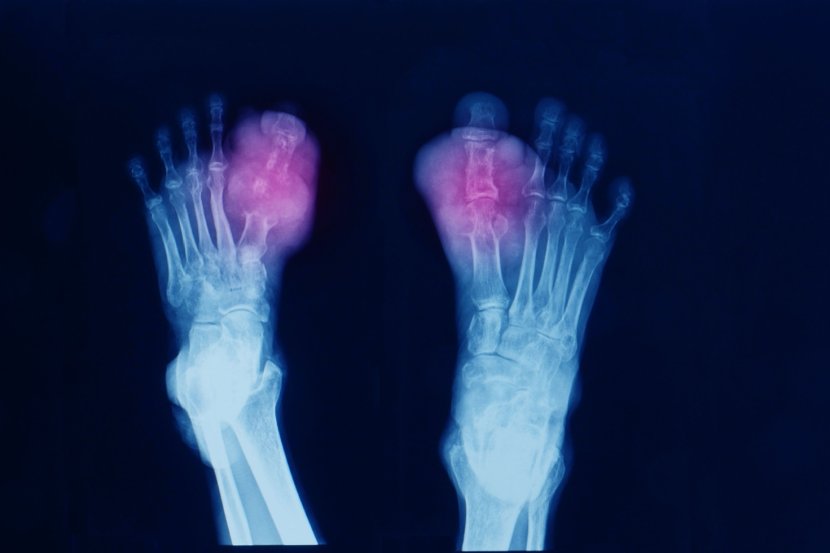

U slučaju kada se mokraćna kiselina ne izbaci iz tela preko urina, višak mokraćne kiseline izaziva hiperurikemiju. Hiperurikemija izaziva zgrušavanje mokraćne kiseline u oštre kristale. Ovi kristali mogu da se talože u zglobovima i izazovu giht - bolan oblik artritisa. Takođe mogu da se nakupe u bubrezima i formiraju kamenje u bubregu.

Simptomi napada gihta u jednom od zglobova su:

Promena boje ili crvenilo

Oticanje

Osetljivost, čak i pri laganom dodiru

Toplina ili osećaj kao da zglob „gori“.